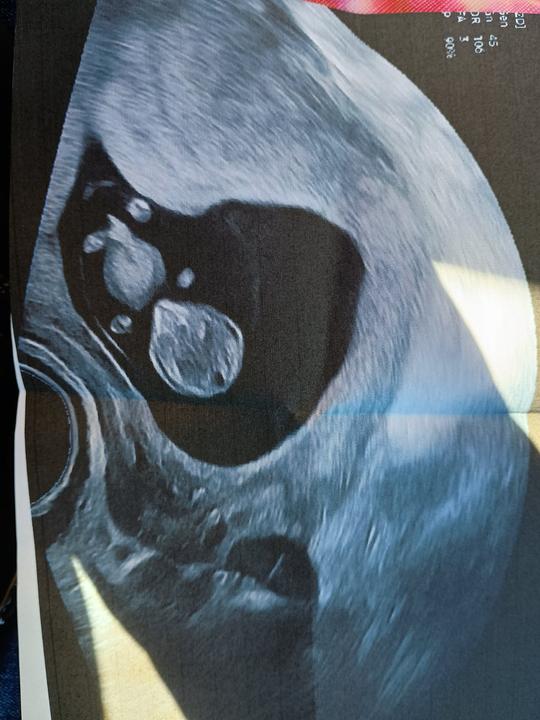

Holky já mám takovou radost 🥳🤩 Dneska jsem byla na kontrole. Všechno je v pořádku, mimčo krásně roste. Když ultrazvuk začal, mimčo tam zrovna mělo diskotéku, mávalo divoce ručičkama a nožičkama. A hned potom se hezky zklidnilo, aby jsme si ho tedy prohlédli a doktorka ho mohla v klidu změřit 😄 Je hodný už takhle v bříšku, snad mu to zůstane i po porodu 😁 Jsem celá naměkko 😍